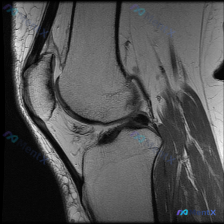

刚整理了一个很有临床意义的病例,核心矛盾是「临床怀疑软骨异常,但现有影像完全正常」,把整个分析思路分享给大家。 病例基础信息 这是一份单张膝关节矢状位T1加权MRI影像,临床提出的核心观察方向是「软骨异常」,无其他临床病史、症状或其他检查资料。 影像具体观察结果 我们先把影像所见说清楚: 1. 骨骼...

看到这个病例挺有代表性的,整理出来和大家分享一下思路。 病例基础信息 这是一张膝关节矢状位T1加权序列MRI影像,用户提出问题:观察图像是否存在软骨异常。 先给大家整理影像评估的基本结果: 1. 骨骼结构:股骨远端、胫骨近端、髌骨皮质连续,骨髓信号未见异常高低信号,关节面形态基本正常 2. 半月板:...

最近遇到一个挺有启发的读片问题,整理出来和大家分享一下: 病例基本情况 这是一份膝关节矢状位T1加权序列MRI,有人提出这份影像可以观察到「软骨异常」,我们先来看详细的影像分析结果: 影像结构整体评估 1. 骨骼结构:股骨远端、胫骨近端、髌骨骨皮质连续,无骨折;骨髓信号正常,无异常低信号提示水肿或占...

病例基础信息 这是一份特殊的膝关节影像评估需求:输入描述提示存在软骨异常 (Chondral abnormality),提供1张膝关节矢状位MRI静态图像,我们先看影像学分析结果: 影像学观察结果 1. 骨骼与软骨:股骨远端、胫骨近端、髌骨骨皮质完整,无骨折,无骨髓水肿;股骨髁、胫骨平台、髌股关节面...

今天整理了一张膝关节MRI的读片分析,这个病例的思路很有代表性,分享给大家。 病例影像基础信息 这是一张膝关节MRI矢状位T1加权像,图像质量良好,对比度清晰,无明显伪影,层面可显示股骨髁、胫骨平台、交叉韧带等核心结构。 系统读片结果 1. 骨与软骨整体情况:股骨远端、胫骨近端骨髓信号均匀,无局灶低...

刚整理了一份有意思的影像读片病例,和大家分享一下思路。 病例基本信息 本次仅提供放射影像-膝盖MRI-T1序列-矢状位单张图像,核心问题是询问图像中是否存在半月板异常。 影像学读片结果 我仔细读了这张片子,所有结构的情况如下: 1. 骨骼结构:股骨远端、胫骨近端、髌骨的骨皮质连续,骨髓信号正常,没有...

刚整理了一份有意思的膝关节MRI读片病例,核心问题是单张T1矢状位图像提示「软骨异常」,这里把整个分析思路整理出来和大家交流。 一、病例基本影像信息 这是一张膝关节正中偏内侧矢状位的T1加权MRI图像,图像质量良好,无明显伪影,可清晰观察髌骨、股骨远端、胫骨近端、后交叉韧带及半月板结构。 二、系统性...